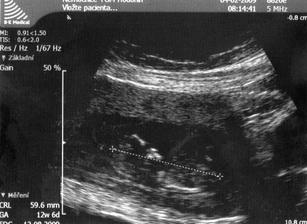

4.2. NT screening.Ultrazvuk dopadl na 1.Ještě čekáme na výsledky krve.Ty by měly být v poradně 19.2.Snad bude i tady vše v pořádku.Máme strach.***********************19.2.odběry na NT screening dopadl na 1.Tak aspoň něco.Na ultrazvuku je mimi o něco menší,ale snad to nebude nic znamenat.Příští týden na krev na TT. 19.3. další poradna.A pak se už pojede do Brna na velký ultrazvuk.***********************************30.3. velký ultrazvuk v brně.Držte nám pěsti,ať je vše OK.****************************************30.3. ultrazvuk v brně dopadl na 1.Mimi je v pořádku a hlavně,čekáme HOLČIČKU.******************************************************************************